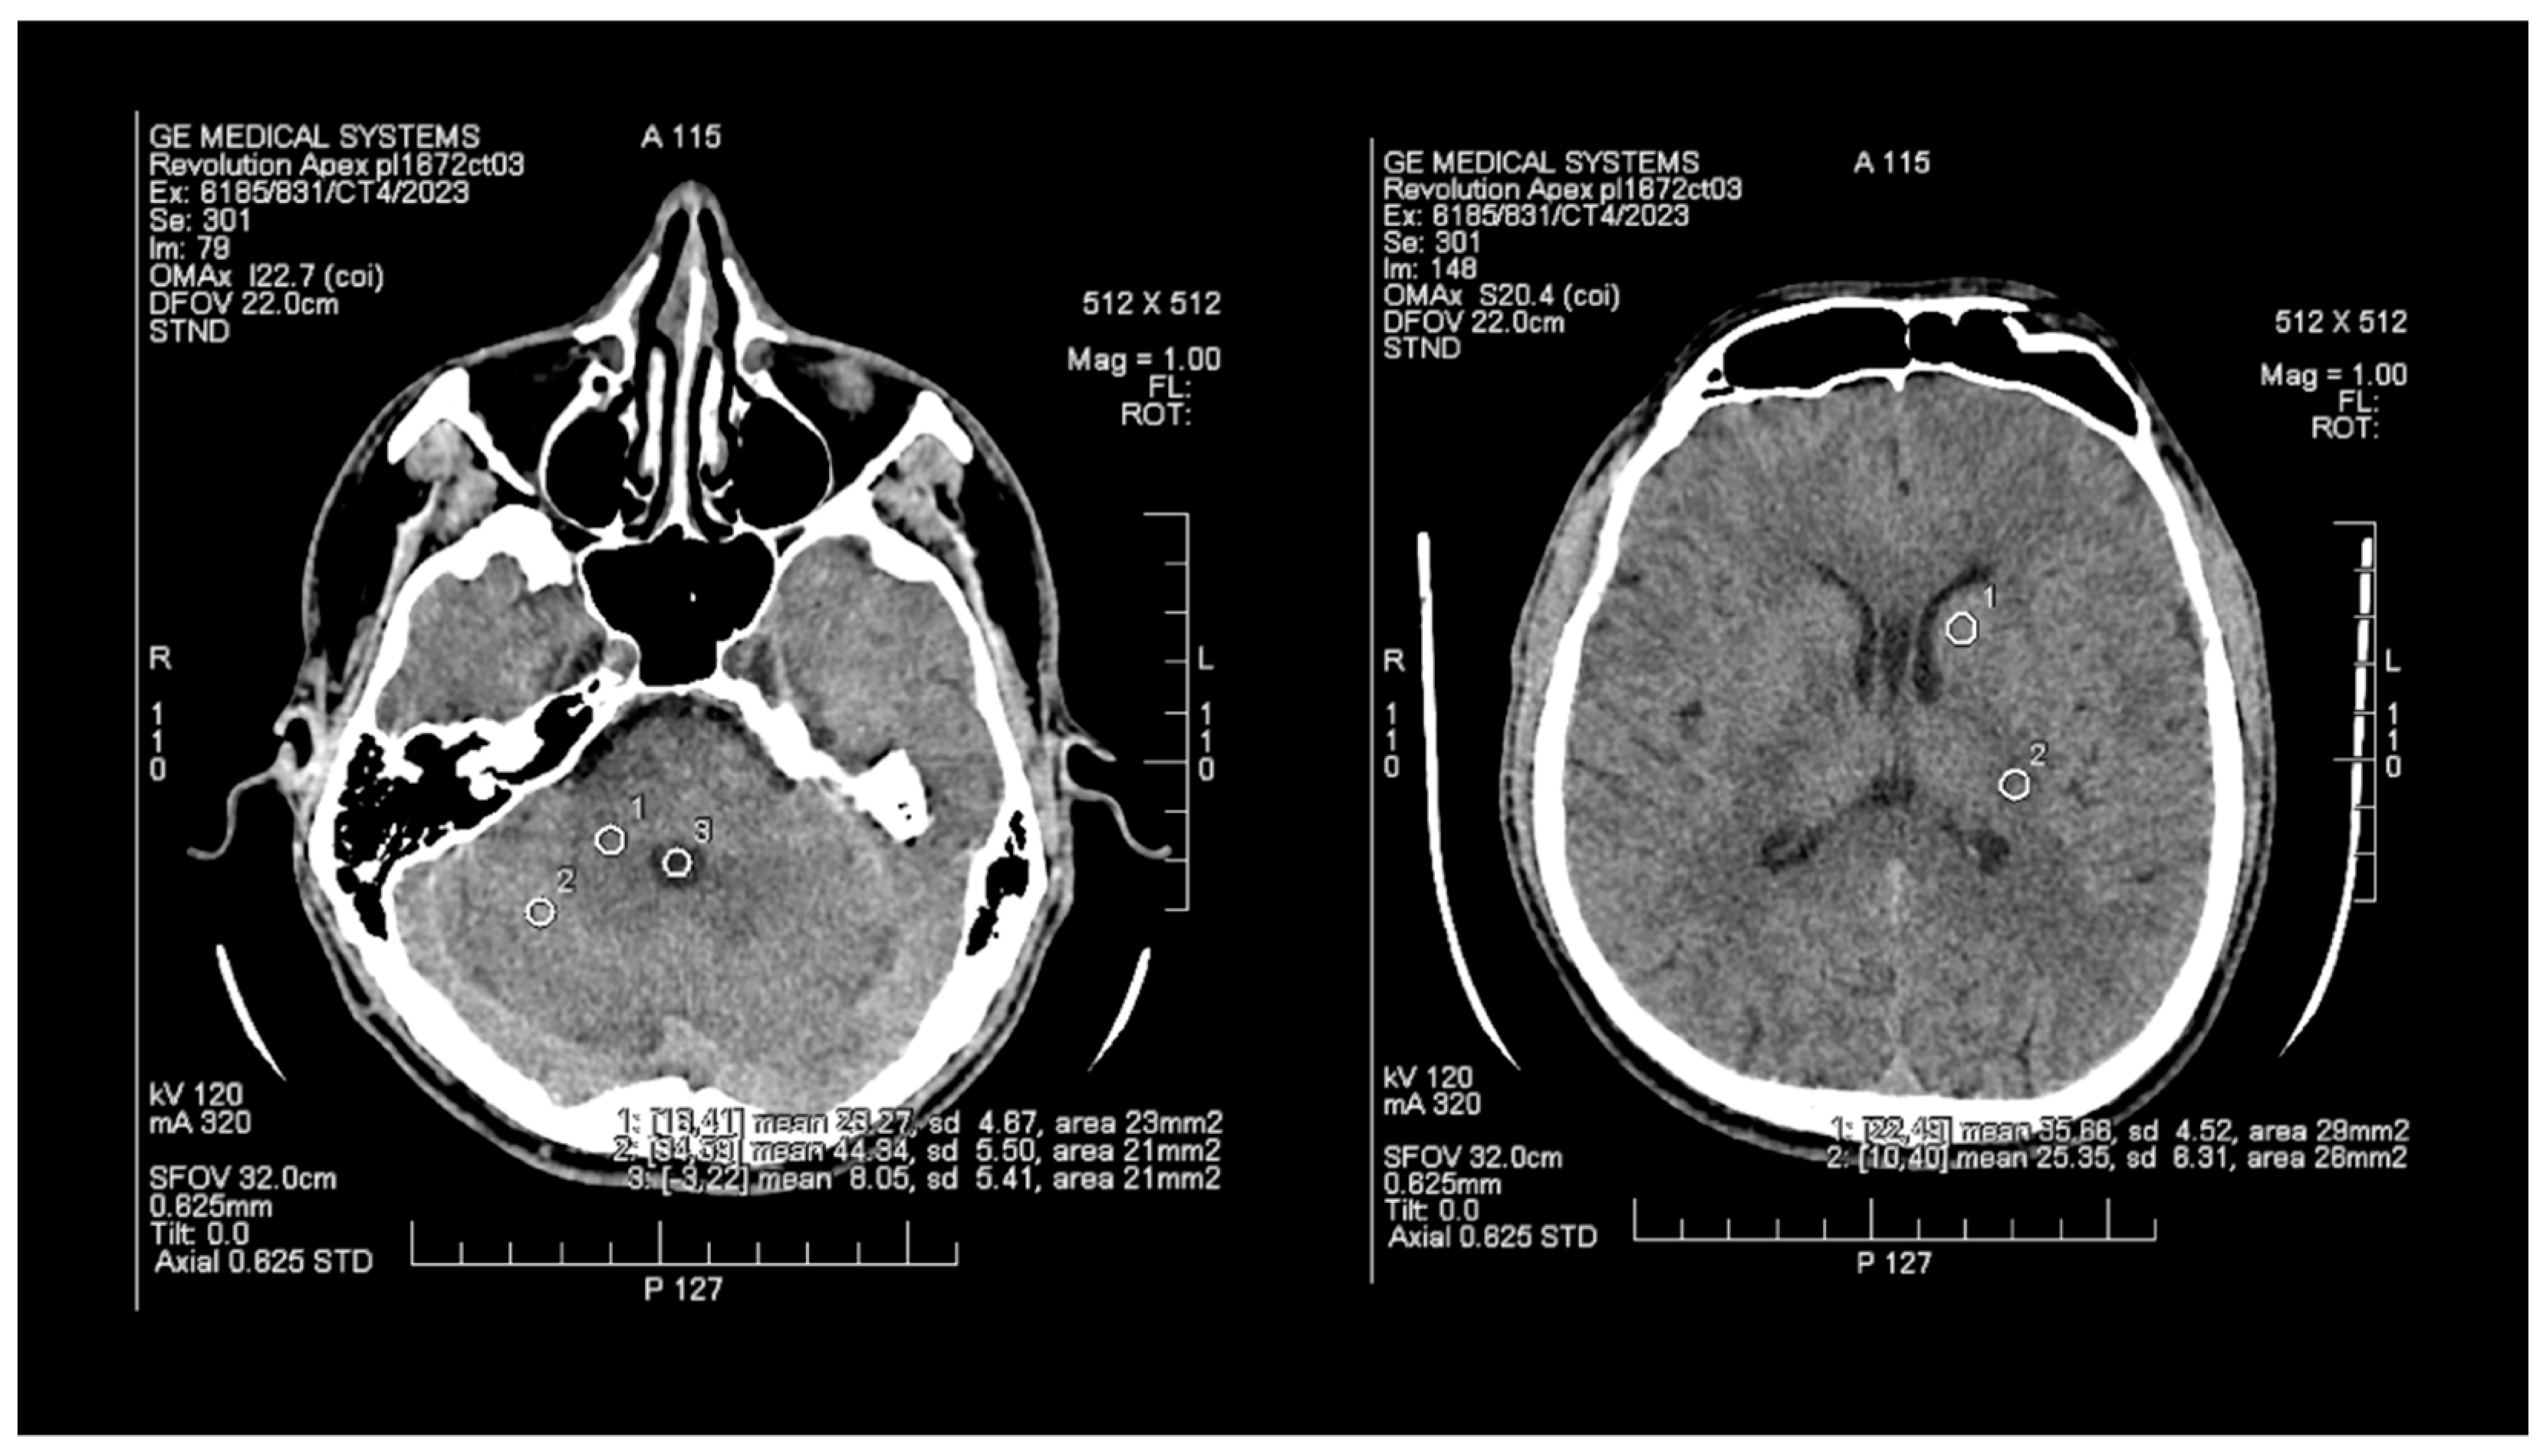

The objective assessment of image quality involved analyzing the signal-to-noise (SNR) and contrast-to-noise (CNR) ratios. To maintain consistency, a control variable was introduced in the form of manually set Regions of Interest (ROIs), which are analogous and predefined study areas in each pair of images. The average size of the ROI area was 24 mm2, with the smallest and the largest areas measuring 20 mm2 and 29 mm2, respectively. ROIs were positioned manually on the ASIR-V (Figure 1) reconstruction image, and then, duplicated at identical coordinates on the DLIR (Figure 2) reconstruction, which excluded potential deviations resulting from the lack of homogeneity of the measured tissues. The designation of the slice subject to the assessment was based solely on the anatomical factors of the patient. The first two ROIs were located in the white matter of the posterior limb of the internal capsule and the grey matter of the caudate nucleus, while the other two ROIs were positioned in the white and grey matter of the cerebellum. The fifth ROI was set in the cerebrospinal fluid of the fourth ventricle. To determine the signal level and noise, the mean CT number (mean) within the ROI and the standard deviation (SD) were taken into account.

Figure 2. Images of head CT with marked ROIs located in BGA (basal ganglia area) and PCF (posterior cranial fossa) obtained using DLIR.